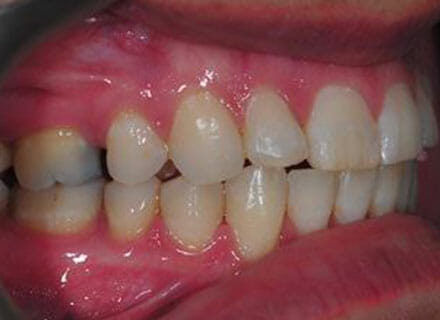

In this case the whole smile was affected by a tooth that was missing (a visible gap or hole at the side when smiling) and a tooth at the front that had grown the wrong side of the bite. We were able to correct the gap at the back by pulling the tooth behind forwards into the gap left by the previous extracted tooth. The clear brace also pushed the tooth at the front back in to the right position and the smile was massively improve. This case took around 18 months to complete.